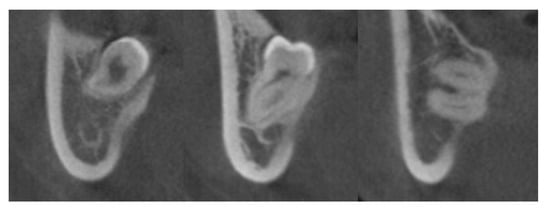

2.3. Surgical Procedure and Identification of IAN Exposure

3.2. Radiographic Characteristics in the Exposed Group